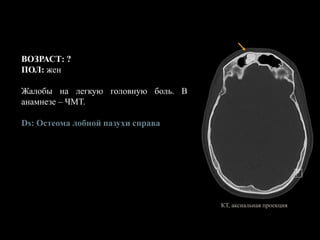

ВОЗРАСТ: ?

ПОЛ: жен

Жалобы на легкую головную боль. В

анамнезе – ЧМТ.

Ds: Остеома лобной пазухи справа

КТ, аксиальная проекция